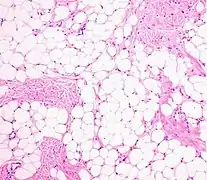

A lipoma is a benign tumor made of fat tissue.[1] They are generally soft to the touch, movable, and painless.[1] They usually occur just under the skin, but occasionally may be deeper.[1] Most are less than 5 cm (2.0 in) in size.[2] Common locations include upper back, shoulders, and abdomen.[4] It is possible to have a number of lipomas.[3]

The many subtypes of lipomas include:[7]:624–5

• A fibrolipoma is a lipoma with focal areas of large amounts of fibrous tissue. A sclerotic lipoma is a predominantly fibrous lesion with focal areas of fat.[12]